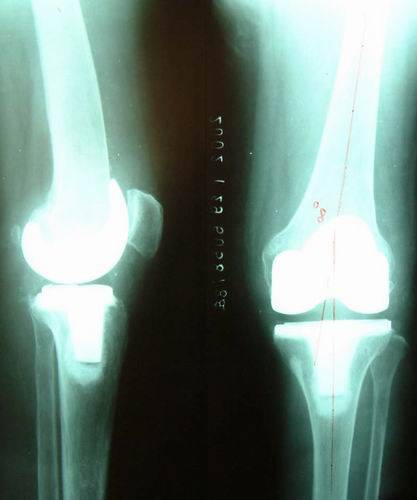

图 膝关节内翻的X线片,膝关节软骨碎裂、磨损,双膝内翻,关节间隙消失。

图、请看她手术后的下肢的X线片,膝关节轴线恢复正常。